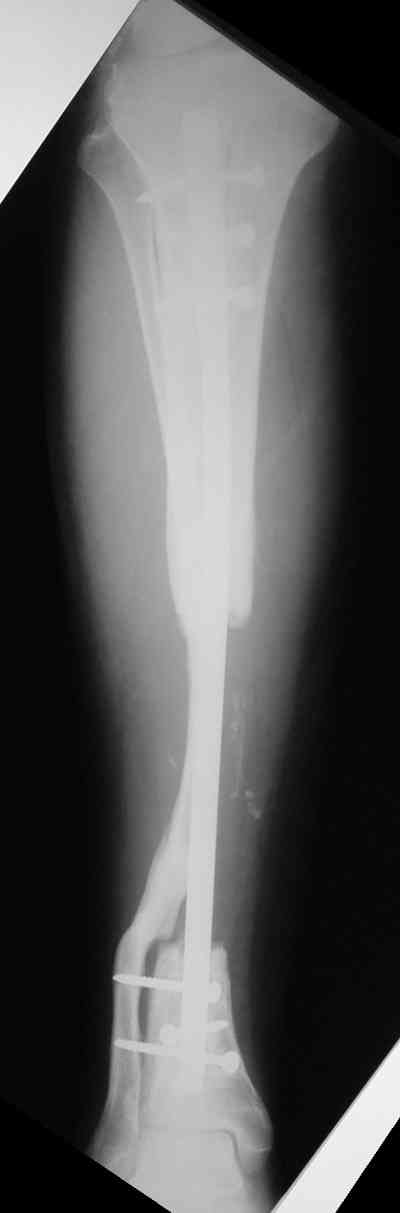

Владимир, свободная костная пластика на фоне свища вряд ли оправдана. Почему не рассматриваете вариант транспорта кости по Илизарову? Что собираетесь делать с латентной инфекцией? Одни антибиотики не помогут, необходима полноценная хирургическая обработка, Мы бы подумали о цементном спейсере с антибиотиками, бусах. После купирования инфекции переходить к замещению

дефекта: за счет удлинения концов б\б кости или тибиализации м\б. На начальном этапе фиксация только в аппарате, в последствие для удержания достигнутого можно перейти на фиксацию интрамедуллярным штифтом (см. вложенные файлы)

Как дополнение высылаю снимки и фото конечности, чтобы Вы могли оценить состояние м/т, и течение заболевания.